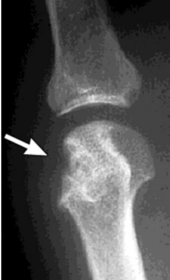

What disease is this? What do the arrows indicate? | Gout Arrows = 'punched out' erosions |